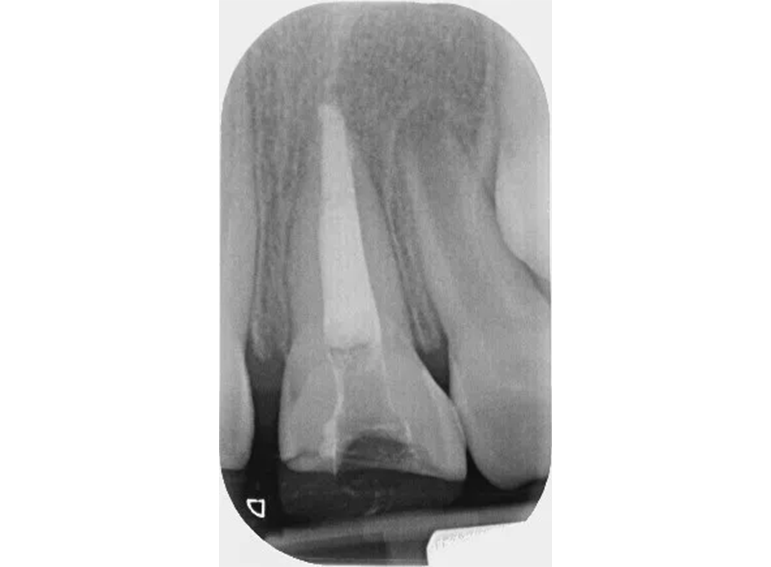

Surgical extrusion, root canal and apexification treatment of UL1 and composite build ups of UR1 and UL1 following dental trauma.